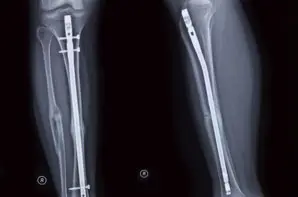

Intramedullary Rods (IM) are metal rods forced into the medullary cavity of a bone. IM rods are used to align and stabilize fractures of long bones. The IM rods are inserted into the bone marrow canal in the center of the bone and stabilize the fracture with bone screws. This device is commonly used when bone fractures are located in the upper arm or leg (Humerus, Tibia, Fibula and Femur). Most often rods placed in long bones to repair a fracture can be left in the patient after full recovery therefore it is critical that medical device manufacturers verify the strength of the implant. ASTM F383 and ASTM F1264 were developed to standardize the quality testing of this device and verify that the product will not fail post-surgery. ASTM F383 was first published in 1973 and has since been withdrawn on account of ASTM F1264′s development.

ASTM F1264 Standard Specification and Test Methods for Intramedullary Fixation Devices outlines four test procedures: